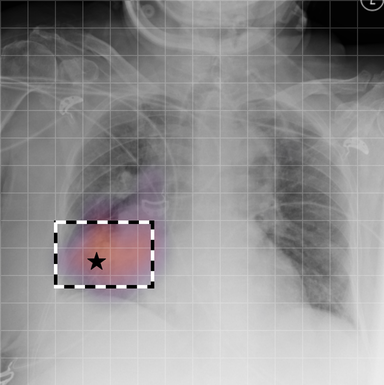

| (1) |

for , where denotes 2D sinusoidal positional encodings [12] and is its temporal counterpart, which is learnt (Fig. 2) [4]. The layer-normalised () [6] output of the final transformer encoder block is an ‘aggregated’ representation of patch-level progression information anchored on the current image. Figure 3 shows attention roll-out [1] applied to after pre-training, showing how the prior image contributes to the fused representation. Figure A.5 further highlights the robustness to variations in pose underlining that registration is not necessary for this encoder.

In Figure A.3, we show examples of self-attention rollout [1] maps for pleural effusion and consolidation, including radiologist-annotated bounding boxes surrounding the corresponding pathology in each prior and current image.

To model the attention flow through the transformer encoder block, we first average each attention weight matrix across all heads, subsequently we multiply the matrices between every two layers. For every block we add the identity matrix in order to model the residual connections. Last, we only keep the top 10 of attention weights per block to reduce noise in the final rollout map. In contrast to [21], we do not visualize the rollout map with respect to a [CLS] token. Instead, we choose a reference image patch from the center of the radiologist-annotated bounding boxes, marked with in Figure A.3.

We find that the rollout maps in Figure A.3 are in good agreement with radiologist-annotated bounding boxes, i.e., the reference patch attends to other patches within the bounding boxes in the prior and current image. In addition, we find that BioViL-T is robust to pose variations, e.g., in Figure A.3 (a) we show that despite the vertical shift between prior and current image, the reference patch attends to the correct image patches in the prior image.

To further assess the robustness of BioViL-T against pose variations between prior and current images, we performed multiple rotations to the prior image within a pair and computed rollout maps from the same reference patch in the current image. Figure A.5 shows that BioViL-T consistently attends to the corresponding anatomical region independently of the spatial transformation applied, demonstrating that registration is not needed.